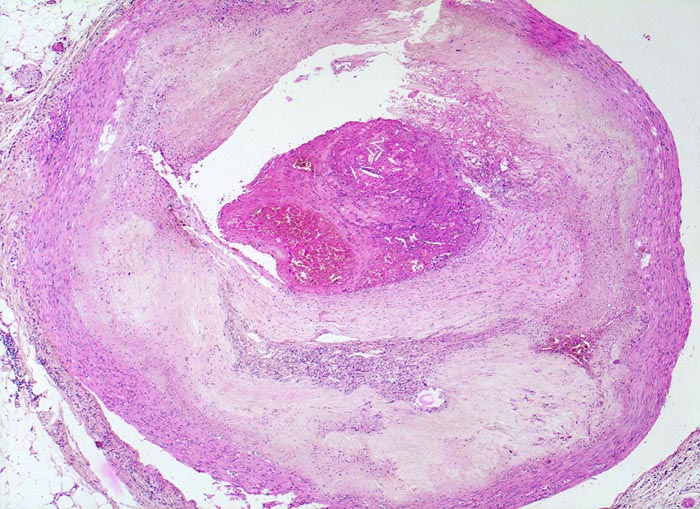

PathoPic – image database / PathoPic ID 4551 - Koronarsklerose mit Thrombose

Koronarsklerose mit Thrombose

Konzentrische Atherosklerose der Koronararterie. Massive Sklerose und Verbreiterung der Intima. Neovaskularisationen in der Intima. Atrophie der Media. Partiell organisierte Thrombose über einem rupturierten Atheromherd. Der Thrombus enthält Cholesterinkristalle aus dem rupturierten Atherom.

Subakuter transmuraler Myokardinfarkt. In der Anamnese Nikotinabusus und schlecht eingestellte arterielle Hypertonie.

Myokardinfarkte treten oft als Folge eines thrombotischen Verschlusses nach Plaqueruptur eines nur mässig stenosierten Gefässes auf (angiographisch 35-65% Stenose). Kleine lipidreiche Atherome rupturieren häufiger als stark fibrosierte Plaques mit schwerer Stenose. Schwere Stenosen führen trotz Tendenz zum thrombotischen Verschluss seltener zu einem Infarkt wegen gut ausgebildeter Kollateralkreisläufe.